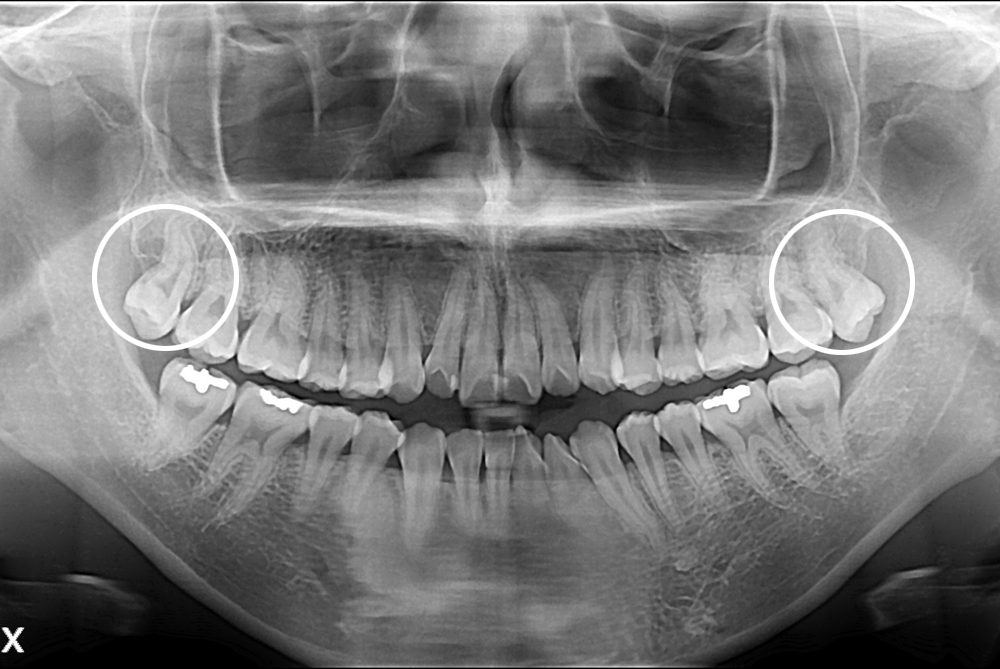

[사랑니] 난발치 사랑니 발치

치료후 : 2017-04-18

세종치과는 구강악안면외과학 박사이신 원장님이 발치하는 치과입니다.